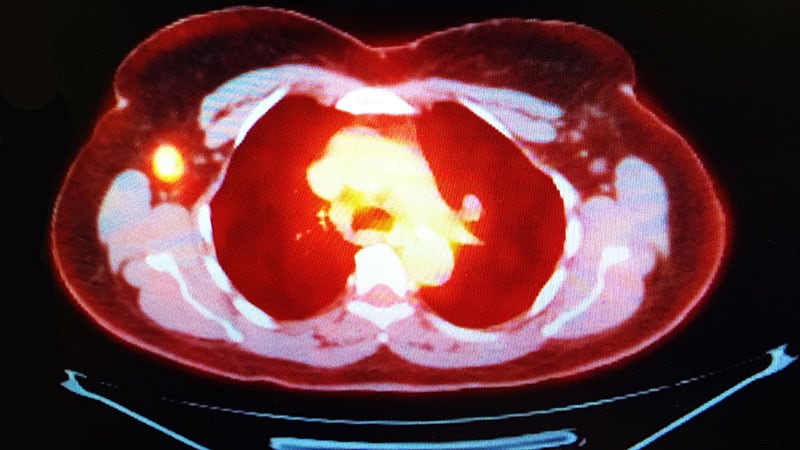

Metastatic Breast Cancer

Survival-Toxicity Trade-off With T-DM1 in HER+ Breast Cancer

HER2+ Combo Shows Promise in Breast Cancer Brain Mets